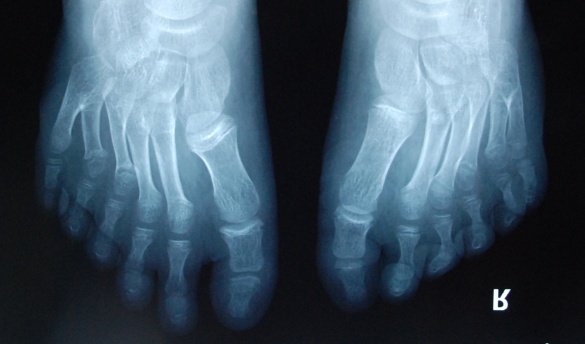

廈門(mén)眼科中心小兒眼科修陽(yáng)暉博士在日常的診療過(guò)程中就接診了不少這樣的的特殊家庭,讓其尤為印象深刻的就是一年前接診的BBS綜合征患者。當(dāng)時(shí)來(lái)院就診的是一對(duì)親兄弟,之前已在多家醫(yī)院做過(guò)檢查,因其均有較大散光和斜視,肉眼下眼底檢查未見(jiàn)異常,故外院均診斷為弱視,這也符合眼科門(mén)診常規(guī)的診斷邏輯與思維。但由于兄弟倆均有智力發(fā)育遲緩、特殊面容及四肢均有六指和六趾的特異體征引起了修陽(yáng)暉博士的警覺(jué):會(huì)不會(huì)是一種特殊遺傳性疾病或綜合征?后續(xù)的檢查結(jié)果進(jìn)一步證實(shí)了修陽(yáng)暉博士的懷疑---患兒均有夜盲,ERG、VEP及OCT檢查顯示雙眼的視網(wǎng)膜神經(jīng)上皮層結(jié)構(gòu)及功能均明顯異常。由于之前未遇到此種病例,修陽(yáng)暉博士在診斷一欄寫(xiě)下視網(wǎng)膜色素變性并打上了個(gè)問(wèn)號(hào),同時(shí)留下了病人的聯(lián)系方式。

BBS綜合征(Bardet-Biedl綜合征)是一種主要累及纖毛結(jié)構(gòu)與功能的罕見(jiàn)常染色體隱性遺傳性疾病。纖毛分布于哺乳動(dòng)物體內(nèi)的大多數(shù)細(xì)胞,它是一種廣泛存在于各種細(xì)胞表面的細(xì)胞器,體型微小但結(jié)構(gòu)復(fù)雜、作用強(qiáng)大,能感知細(xì)胞外機(jī)械和化學(xué)信號(hào)變化并協(xié)助其轉(zhuǎn)導(dǎo)到細(xì)胞內(nèi)部從而引起細(xì)胞應(yīng)答。高等動(dòng)物的視覺(jué)、觸覺(jué)、嗅覺(jué)、聽(tīng)覺(jué)的傳遞都依賴于體內(nèi)外正常的纖毛結(jié)構(gòu)和功能。因此BBS綜合征常累及全身多個(gè)系統(tǒng)和器官,在臨床上主要表現(xiàn)為:視網(wǎng)膜色素變性、智力發(fā)育異常、向心性肥胖、多指(趾)、性腺發(fā)育異常、腎臟異常。除此之外還有許多諸如:語(yǔ)言發(fā)育障礙、聽(tīng)力異常、嗅覺(jué)異常、斜視、白內(nèi)障、散光、牙齒發(fā)育異常、短指(趾)、并指(趾)、肝纖維化、糖尿病、高血壓等表現(xiàn)。